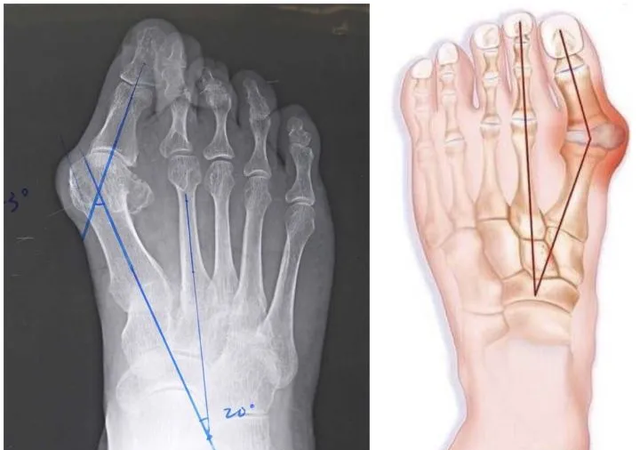

倘若再配上窄鞋头,脚趾头严重受到挤压、弯曲异常,还会加剧「拇外翻」的形成。

幸运飞艇开奖网 X 线片中可明显看到踇外翻的结构改变